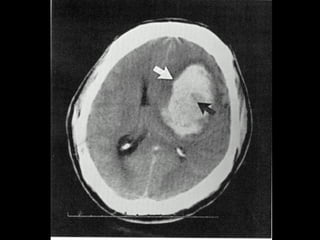

Traumatism cranio-cerebral prin împuşcare – hemoragie frontalăTraumatism cranio-cerebral prin împuşcare – hemoragie frontală

bilaterală, contuzie parietală şi hemoragie subarahnoidianăbilaterală, contuzie parietală şi hemoragie subarahnoidiană